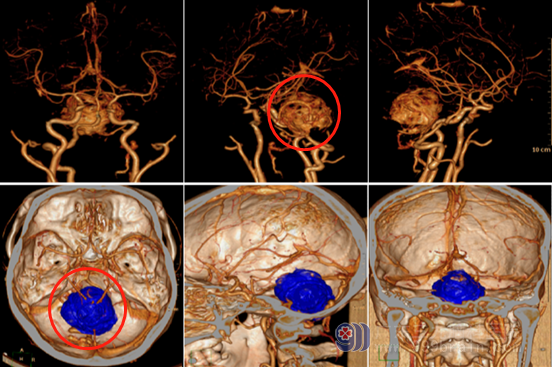

▲术前DSA和CTA

医院副院长、神经外五科主任鲁明指示,患者为起源小脑蚓部突入四脑室的血管母细胞瘤,无家族史,腹部CT及全脊髓未见病变,考虑颅内单发病变。此肿瘤血管异常丰富,需要术前准确判断及术前的充分准备,更需要术中的精湛技术,才能避免大出血或切除不彻底情况。术后仍需注意再出血风险,同时肿瘤位置位于脑干背面,应尽可能避免脑干损伤,还要关注术后脑积水缓解情况。

手术尽管困难,但这是挽救病人的唯一希望,经过多次谨慎的病例讨论,决定先行术前栓塞,将肿瘤部分供血血管堵住,再行手术彻底切除。手术方案得到了小洪及家人的认可。术前栓塞顺利;手术按计划进行,打开颅腔后可见明显的较多供血动脉环绕肿瘤,虽然做了部分栓塞仍存在较多血管,肿瘤位于脑干的背面,瘤体紧贴延髓;先游离肿瘤周边供血血管,并使用动脉瘤夹阻断必要的动脉,同时保护好重要的引流静脉,游离阻断血管后再逐步将肿瘤完整剥离,肿瘤大小4.8cm×4.8cm×5.2cm,脑组织及血管保护良好,完美地避免了大出血,术中出血约150ml。病理结果证实了肿瘤为血管母细胞瘤。